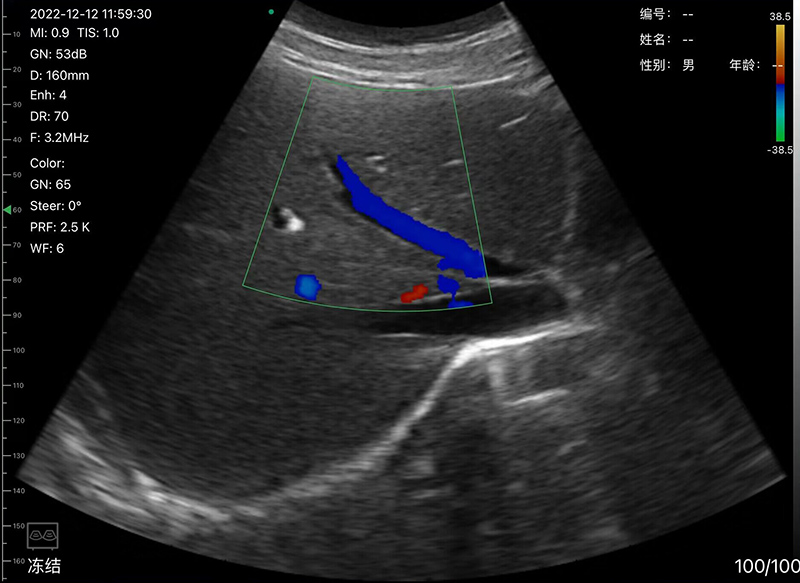

• Scan mode: Electronic Array Convex scanning

• Frequency: Convex probe 3.2/5.0MHz

• Display mode: B, B/M, Color, PDI, PW